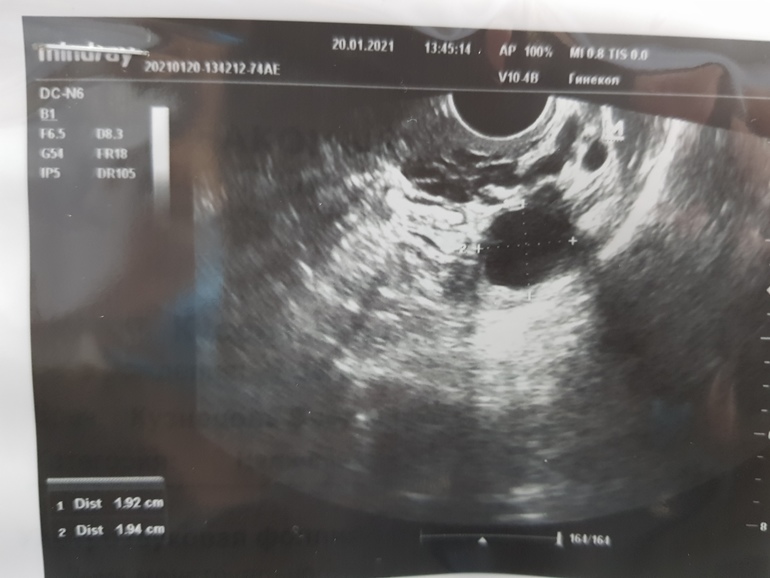

День цикла 11й.

Была на узи на 8й: ЛЯ 16мм, ПЯ 16, 14, 14

На 11й: ЛЯ 19мм, ПЯ 16, 15, 14.

Сказала все фоликулы. На 8й врач думала кисты, но я на стимуляции и проверяла до, что кист нет.

Где-то на этих фотах спряталось аж 4 штуки, сказали дф, но должны быть уже жт. На стимуляции.

На 8й дц было 16мм один дф в левом и 16, 14, 14 в правом. На стимуляции.

А на 11й дц сказали что 19мм один в левом и 16, 14, 14 в правом.

Вот я и думаю как так, до 8го дц вымахали и замерли.

Я ожидала что будут жт (до 4х, на стимуляции), но мне сказали что ДФ. Просто на 8й дц они были 16, 16, 14, 14, а на 11й стали 19, 16, 14, 14.